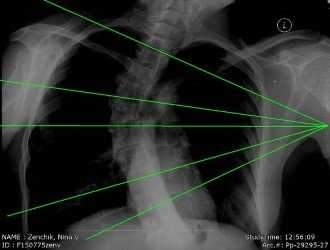

На прямом заднем снимке видны тела грудных позвонков, имеющих форму прямоугольников, ножки дуг в виде симметричных овалов, наслаивающихся на изображение верхнебоковых отделов тел, поперечные и остистые отростки. В верхнем отделе остистые отростки проекционно накладываются на изображение соответствующих тел позвонков, в нижнем отделе они проецируются на тела нижележащих позвонков. Промежутки между телами позвонков представляют собой межпозвоночные диски; высота их, так же как и размеры тел позвонков, постепенно увеличивается по направлению книзу.

Хорошо видны головки ребер, образующие суставы с телами позвонков, а в нижнем отделе также и бугорки ребер, образующие суставы с поперечными отростками (рис. 228).

На технически правильно выполненном снимке хорошо видна структура тел позвонков; четко определяются контуры тел позвонков, ножек дуг, отростков и ребер.

Правильность укладки устанавливают по симметричности изображения ножек дуг, а также по проекционному отображению остистых отростков соответственно срединной линии позвоночника. Ошибки в укладке больного при выполнении данного снимка обычно не встречаются